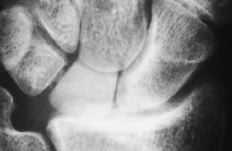

Figura 5. En la radiografía de perfil se aprecia la inestabilidad en DISI del implante.

ABFigura 6. Imágenes líticas intraóseas de predominio hueso grande-piramidal. A: Radiológica. B: Tomografía computerizada.

Debido a esta falta del implante hemos observado en un 20% de los casos luxación y subluxación de la artroplastia, en un 30% inestabilidad en DISI y en un 10% en VISI. La incidencia de imágenes líticas intraóseas y sinovitis por liberación de partículas de silicona en nuestra serie es del 40%. Surgen por la abrasión y el desgaste del implante y producen una sinovitis hipertrófica con granulomas por silicona.19 Microscópicamente se aprecia la respuesta del huésped a estas partículas como una reacción de células gigantes a cuerpo extraño. Los leucocitos y macrófagos fagocitan el material, pero la silicona no se afecta por las enzimas lisosomales, lo que induce una sinovitis reactiva que no es exclusiva de la silicona (PMMA, polietileno y otros materiales metálicos), estando siempre en relación con el tamaño de la partícula. Las partículas de silicona son de 30 a 60 micras de diámetro. Estos implantes se han desaconsejado para la sustitución del escafoides y del semilunar, ya que al estar sometidos a importantes cargas de compresión se produce su fragmentación.31 Los factores que desgastan el implante de silicona y contribuyen a la formación de partículas son las fuerzas excesivas a través del implante debidas a la asociación de inestabilidad o de colapso, una malposición o exceso de tamaño, exceso de movilidad y abuso de la actividad diaria.43,44